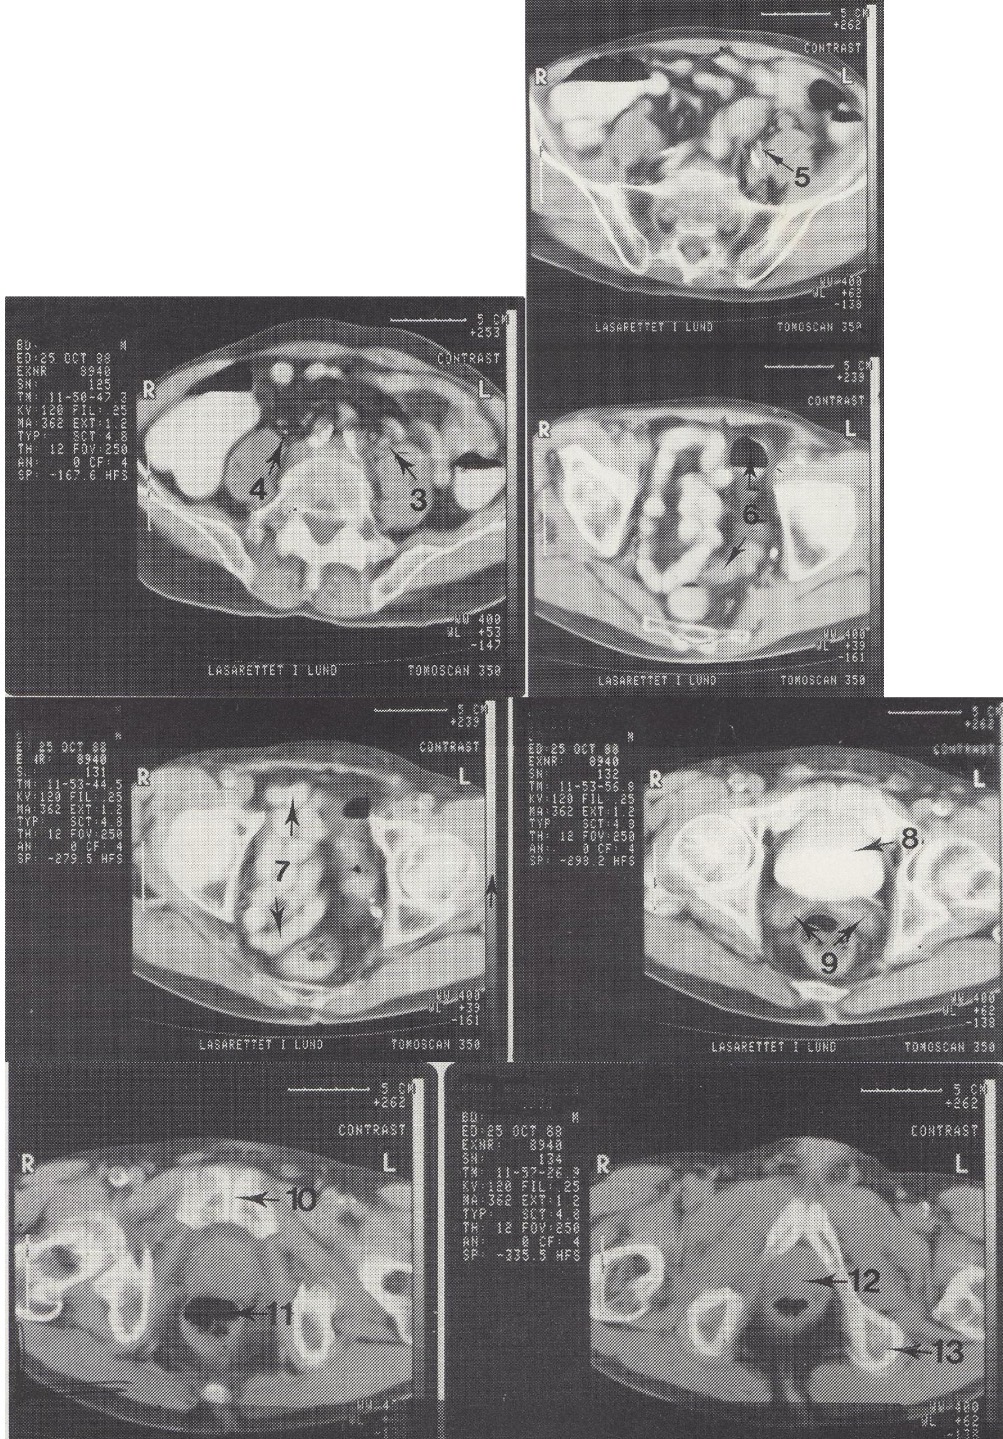

5

A. iliaca interna sin. (kairioji vidinė klubo arterija)

6

Colon sigmoideum (riestinė žarna)

7

Ileum kilpos dubenyje (tuščiosios žarnos kilpos)

Metodika

KT pjūviai nuo juosmens slankstelių iki gaktinės sąvaržos apačios. Suleistas intraveninis kontrastas (išryškina šlapimo takus) ir išgertas kontrastas (išryškina žarnyną).

Radiniai

Gausūs apkalkėjimai (kalcifikatai) aplink pilvinę aortą ir vidines klubo arterijas. Kairysis šlapimtakis matomas priešais m. psoas major, jis šiek tiek išsiplėtęs.